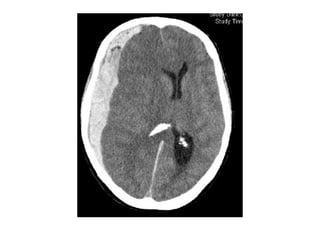

-Acute thrombus is hyperdense on precontrast CT

and expands the occluded sinus / vein (Dense

clot sign)

- Cord sign : is defined as a homogeneous ,

hyperattenuated appearance of thrombosed

venous sinuses , the hyperattenuated

appearance of the affected veins often being

Direct visualization of a clot in the cerebral veins on a non enhanced

CT scan is known as the dense clot sign

Dense clot sign in a thrombosed cortical vein

Hemorrhagic infarction in the temporal lobe (red arrow) , notice the dense

transverse sinus due to thrombosis (blue arrows)